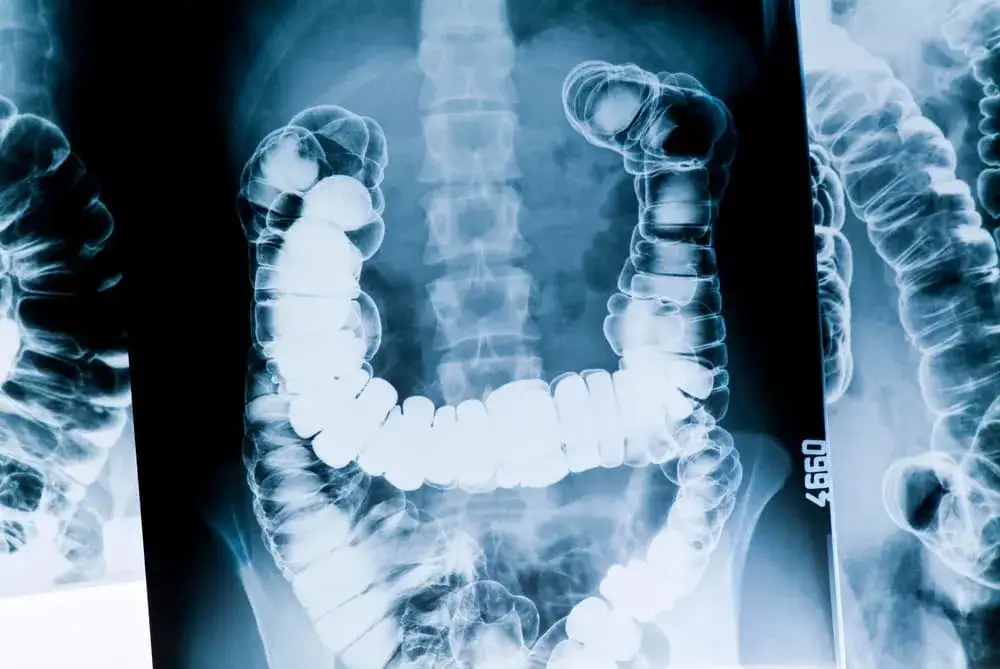

Wgłobienie jelita to poważny stan, który może wystąpić u niemowląt, a jego objawy często budzą niepokój wśród rodziców. Wczesne rozpoznanie i interwencja są kluczowe, aby uniknąć poważnych komplikacji zdrowotnych. Najczęściej dotyczy chłopców w wieku od 3 do 12 miesięcy i objawia się m.in. kolkowym bólem brzucha, wymiotami oraz ogólnym złym samopoczuciem.

Wgłobienie jelita to stan, który może być niebezpieczny dla niemowląt. Wczesne rozpoznanie objawów jest kluczowe, aby uniknąć poważnych komplikacji zdrowotnych. Dzieci najczęściej doświadczają kolkowego bólu brzucha, co jest jednym z pierwszych sygnałów, które powinny zaniepokoić rodziców.

Przyczyny wgłobienia jelita u niemowlaka i ich znaczenie

Wgłobienie jelita najczęściej występuje u niemowląt, zwłaszcza chłopców w wieku od 3 do 12 miesięcy. Przyczyny tego stanu mogą być różnorodne, w tym anatomiczne uwarunkowania i czynniki genetyczne. Warto zwrócić uwagę na to, że w niektórych przypadkach przyczyny mogą być trudne do ustalenia, co sprawia, że rodzice powinni być szczególnie czujni.

Częstość występowania wgłobienia jelita wśród niemowląt

Statystyki wskazują, że wgłobienie jelita występuje u około 2-4 na 1000 niemowląt. To stosunkowo rzadkie, ale poważne schorzenie, które wymaga natychmiastowej uwagi. Warto zauważyć, że chłopcy są bardziej narażeni na ten stan niż dziewczynki, co może być związane z różnicami anatomicznymi.